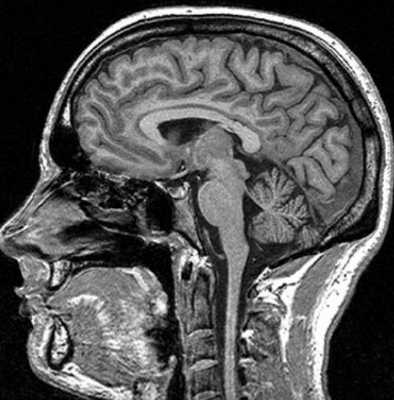

Гемосинус на МР-снимке головы

Внутримозговая гематома травматического характера на МР-снимке